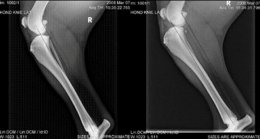

De kruisbanden zijn twee banden die in de knie kruislings tussen het scheenbeen en het dijbeen gespannen zitten. Ze dienen om deze botten stabiel te houden ten opzichte van elkaar. Het is meestal de voorste kruisband die scheurt. Als deze band kapot is wordt de knie instabiel. Het dijbeen en het scheenbeen kunnen nu over elkaar schuiven waardoor de meniscus, die tussen deze botten ligt, ook kan scheuren.